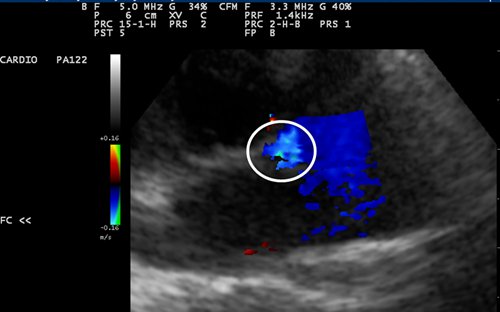

Doppler couleur

Flux turbulent qui confirme qu’il existe bien ici une membrane avec une turbulence.

Diminution de diamètre peu importante car vitesse peu importante